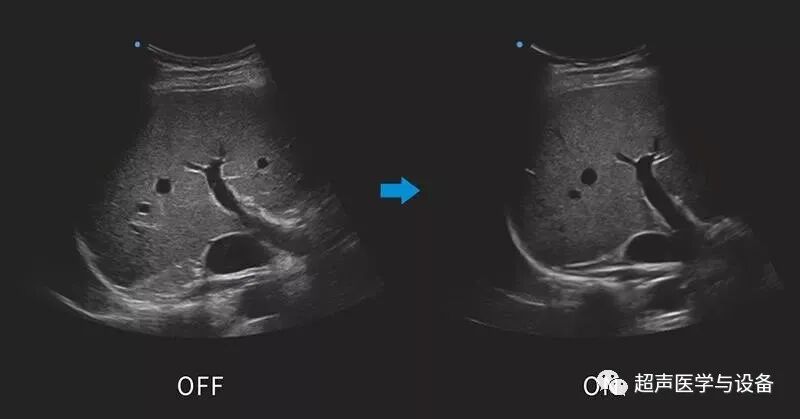

全域聚焦

全域聚焦近些年几乎成了所有超声厂家高端彩超的标配,它打破了传统波束中场聚焦的限制,目的改善图像近中远场的图像质量,尤其是近场和远场图像信息更多,更有利于复杂疾病的诊断。SIUI的全域聚焦自动补偿信号在组织内传播过程中的非线性误差,提高成像的聚焦的精确度和一致性,实现图像声场从近到远的均匀一致。

siui彩超怎么用第84届CMEF超声厂家“群英会”---汕头超声:中国超声行业的“老大哥”_https://www.jmylbn.com_新闻资讯_第29张

图 / 全域聚焦